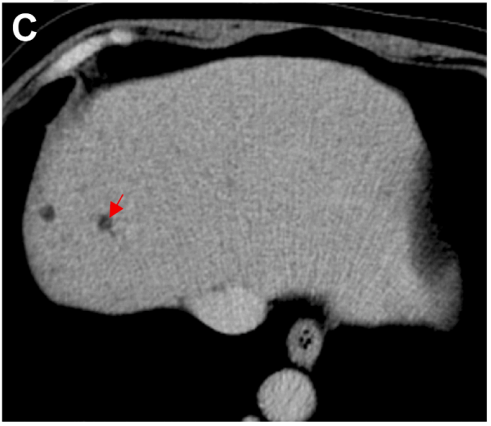

病史摘要:61岁男性患者,因反复发热和右上腹痛1个月内3次住院。首次因发热、右上腹轻度疼痛入院,血培养检出大肠埃希菌;第二次出院4天后因高热、右上腹轻度疼痛再次入院,血培养仍为大肠埃希菌;第三次出院3天后因高热、右上腹痛加重入院,血培养依旧是大肠埃希菌。 诊疗过程:首次及第二次入院均用哌拉西林 - 他唑巴坦治疗,第三次入院实验室检查炎症指标变化大,血培养仍为大肠埃希菌